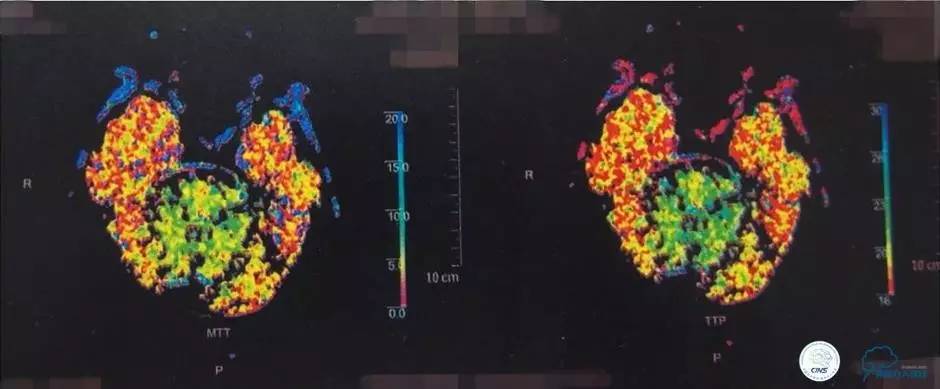

▼颅脑CT灌注扫描

▼2014-12-08